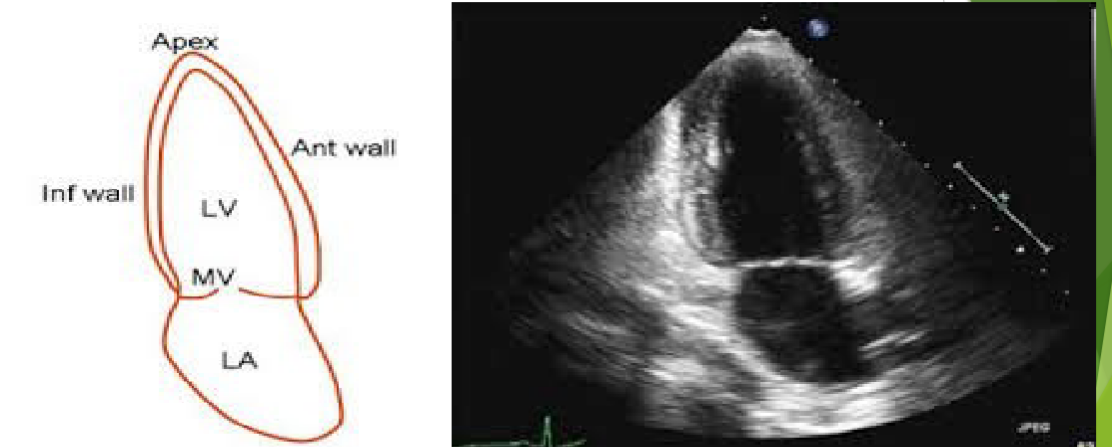

<p>Which of the following window is Apical Window?</p>

Which of the following window is Apical Window?

2

New cards

<p>What view is this?</p>

What view is this?

Apical 4 Chamber